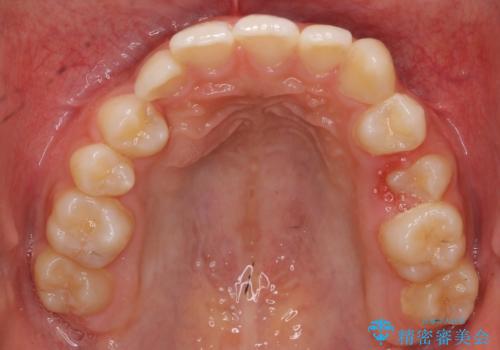

- 右上の犬歯が埋伏していたため、抜歯しました。

その後、右下の小臼歯を1本抜歯し、ワイヤー矯正を行いました。

犬歯の代わりに小臼歯を配列し、最小限の抜歯の本数としました。

犬歯の両側の歯に関しては移動することにより歯槽骨が順調に回復し、上顎洞底の形態にかかわらず歯根のパラレリングを行うことができました。

犬歯の両側の歯に関しては移動することにより歯槽骨が順調に回復し、上顎洞底の形態にかかわらず歯根のパラレリングを行うことができた理由としては、年齢が10代前半と若かったからだと思います。

左上4−7については、近心傾斜をしていたため、右上3を抜かずに遠心に移動して非抜歯で治療を行う案も提案しましたが、抜歯を選択されました。結果的に深く埋まっていた右上犬歯を牽引せずにすみ、さらに歯根の向きも整えることができてよかったです。治療も比較的短期間で済みました。